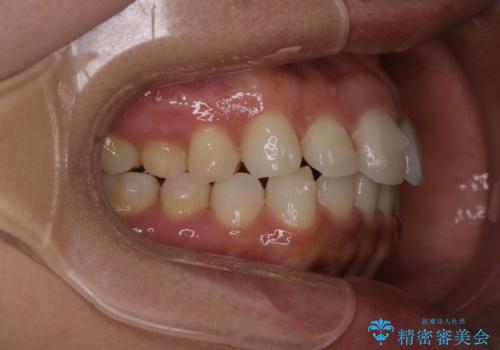

【インビザライン】前歯の後戻りを再矯正

- 前歯が出ていることを主訴に来院されました。検査の結果、口元が標準より出ているわけではなかったため今回はIPRと拡大をし、非抜歯で治療を行いました。

非抜歯でも歯軸の向きを改善したことで前歯が下がり、出っ歯に見えてしまうという主訴が改善しました。